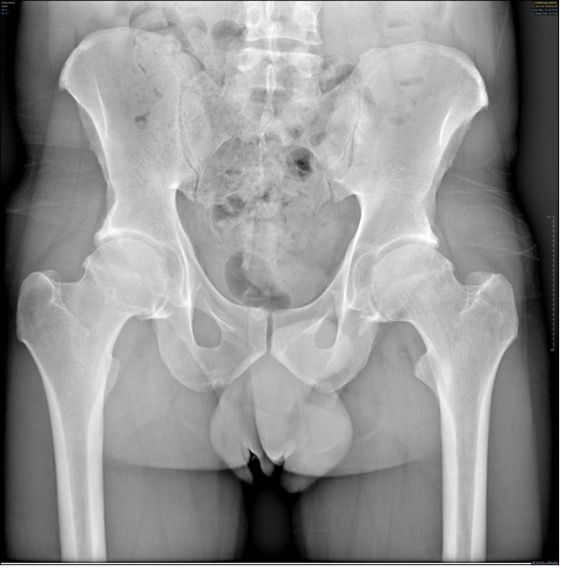

The clinical articles in this issue address several dimensions of hip arthroplasty practice. Topics include revision total hip arthroplasty using cementless stems with bioactive coatings, lessons from 34 years of hydroxyapatite clinical experience, and the rationale for calcar-guided short stems. Further contributions examine total hip arthroplasty in patients with low bone mass and the role of personalized hip joint replacements using large diameter heads in optimizing anatomical restoration and long-term implant performance.